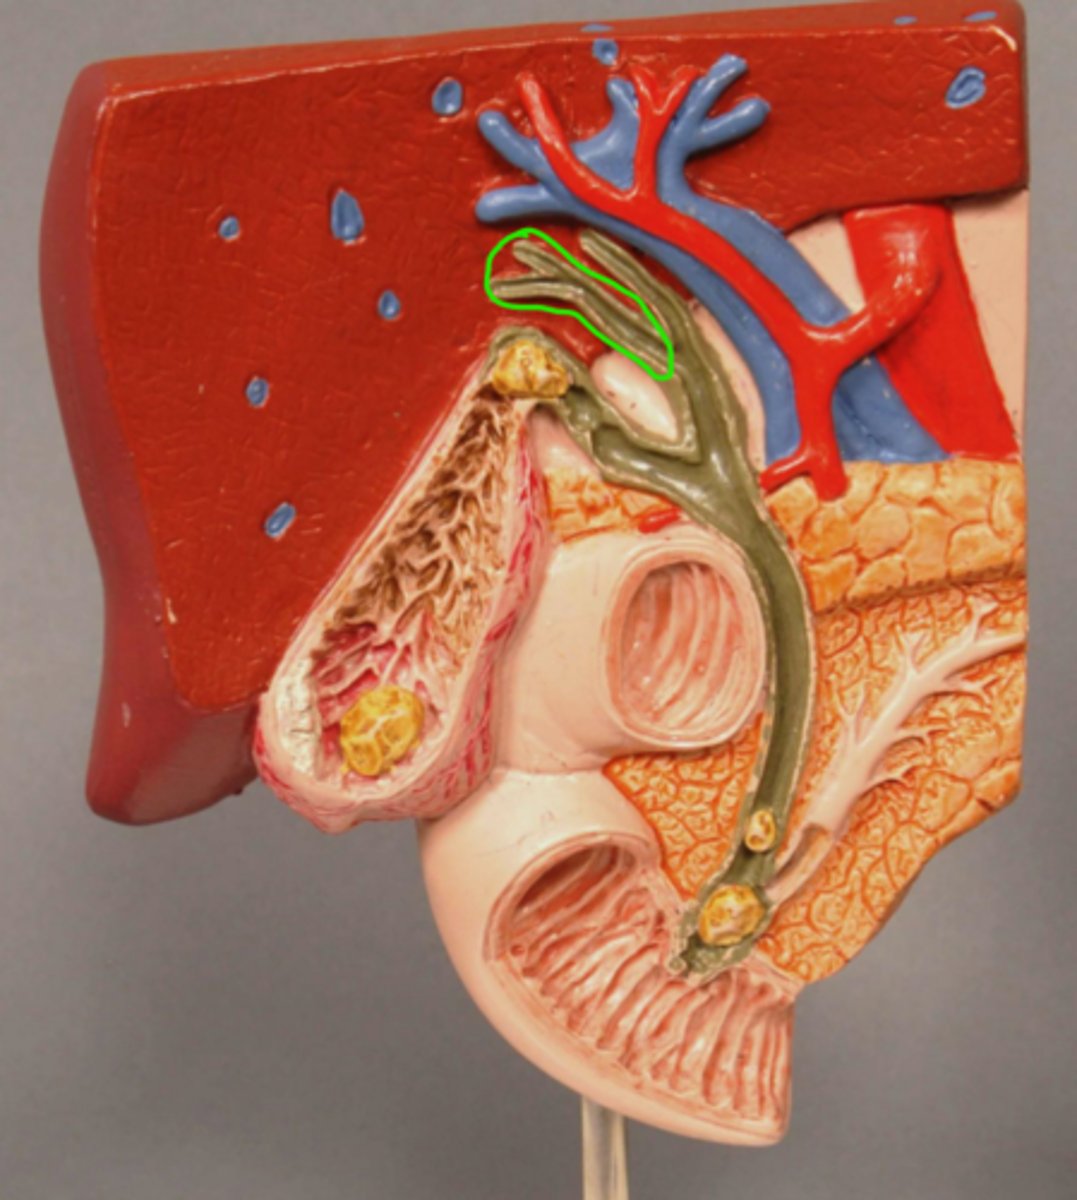

Gallstone Model

Gallbladder

Gallbladder Mucosa

Cystic Duct

Gallstone in Fundus of Gallbladder

Gallstone at entrance to cystic duct

Acute Inflammation of Gallbladder (Cholecystitis)

Scarred wall of Gallbladder (Following Chronic Inflammation)